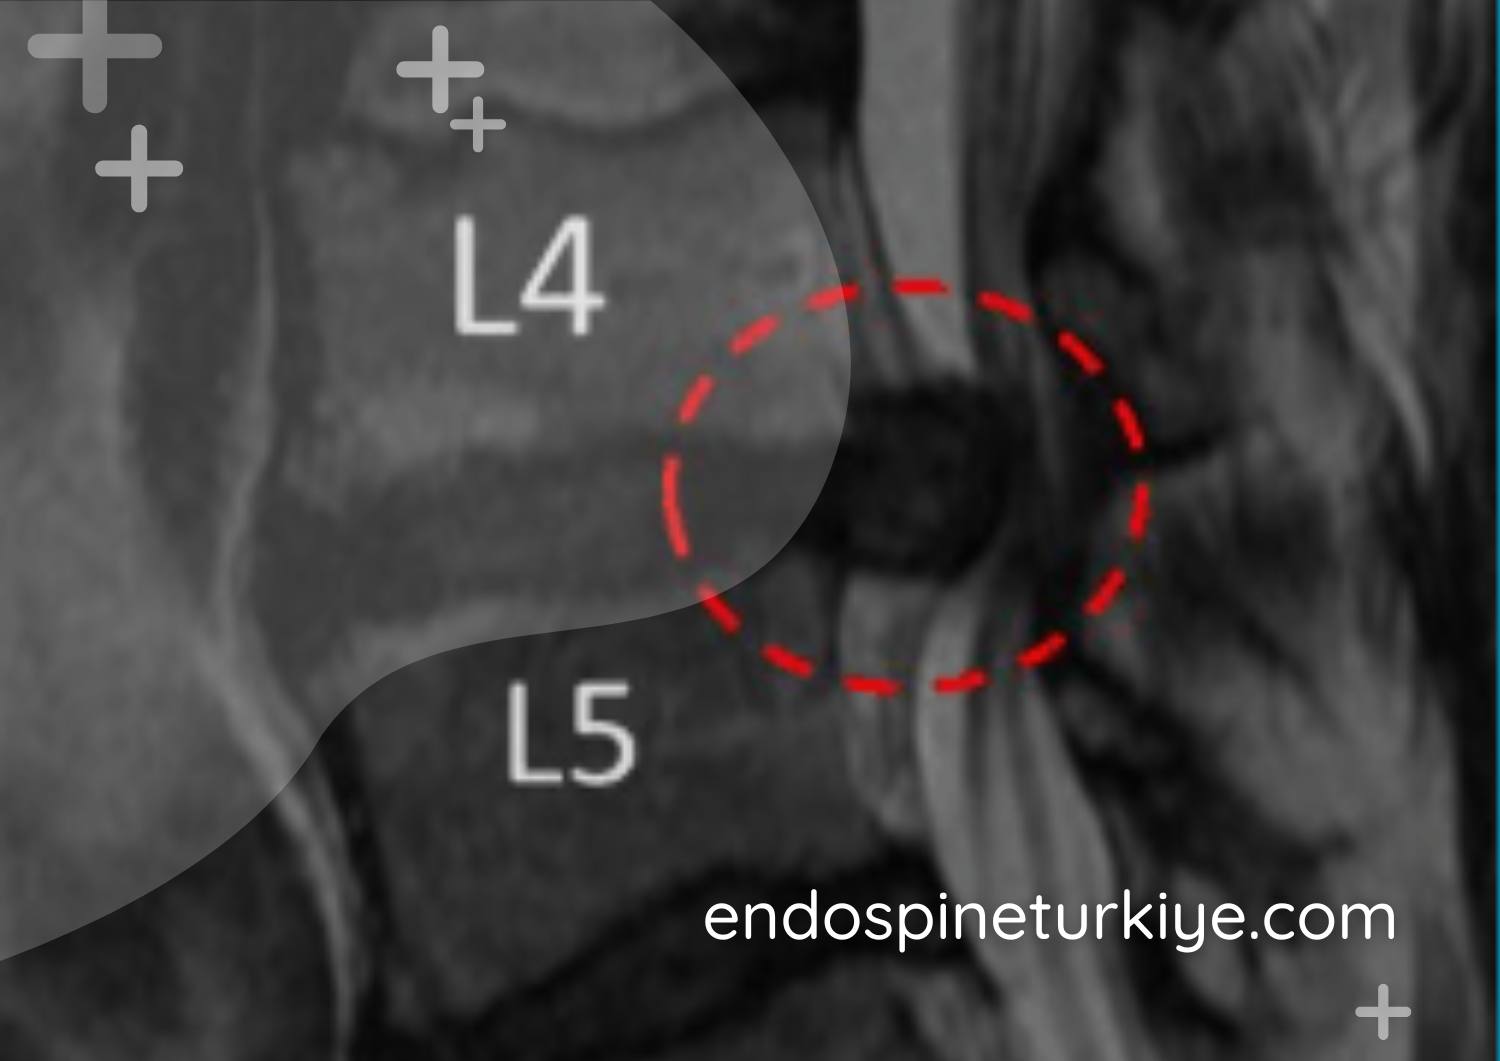

Foraminal Stenoz

Sinir kökü çıkış kanalının daralması. Üst ya da alt ekstremitelere yayılan ağrı.